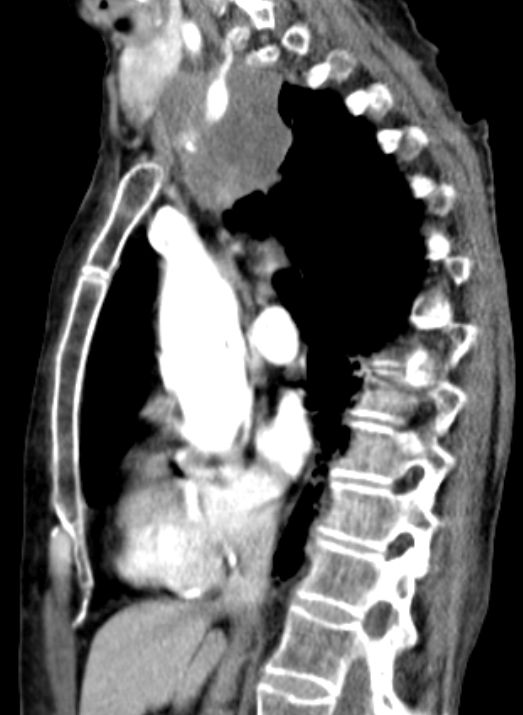

| Wirbelinfiltration | Pancoast - Tumor rechts mit Infiltration der

Wirbelsäule und Erreichen der Speiseröhre. Klinisch Parese des rechten Arms.

Schlucken nicht beeinträchtigt. ![]() |